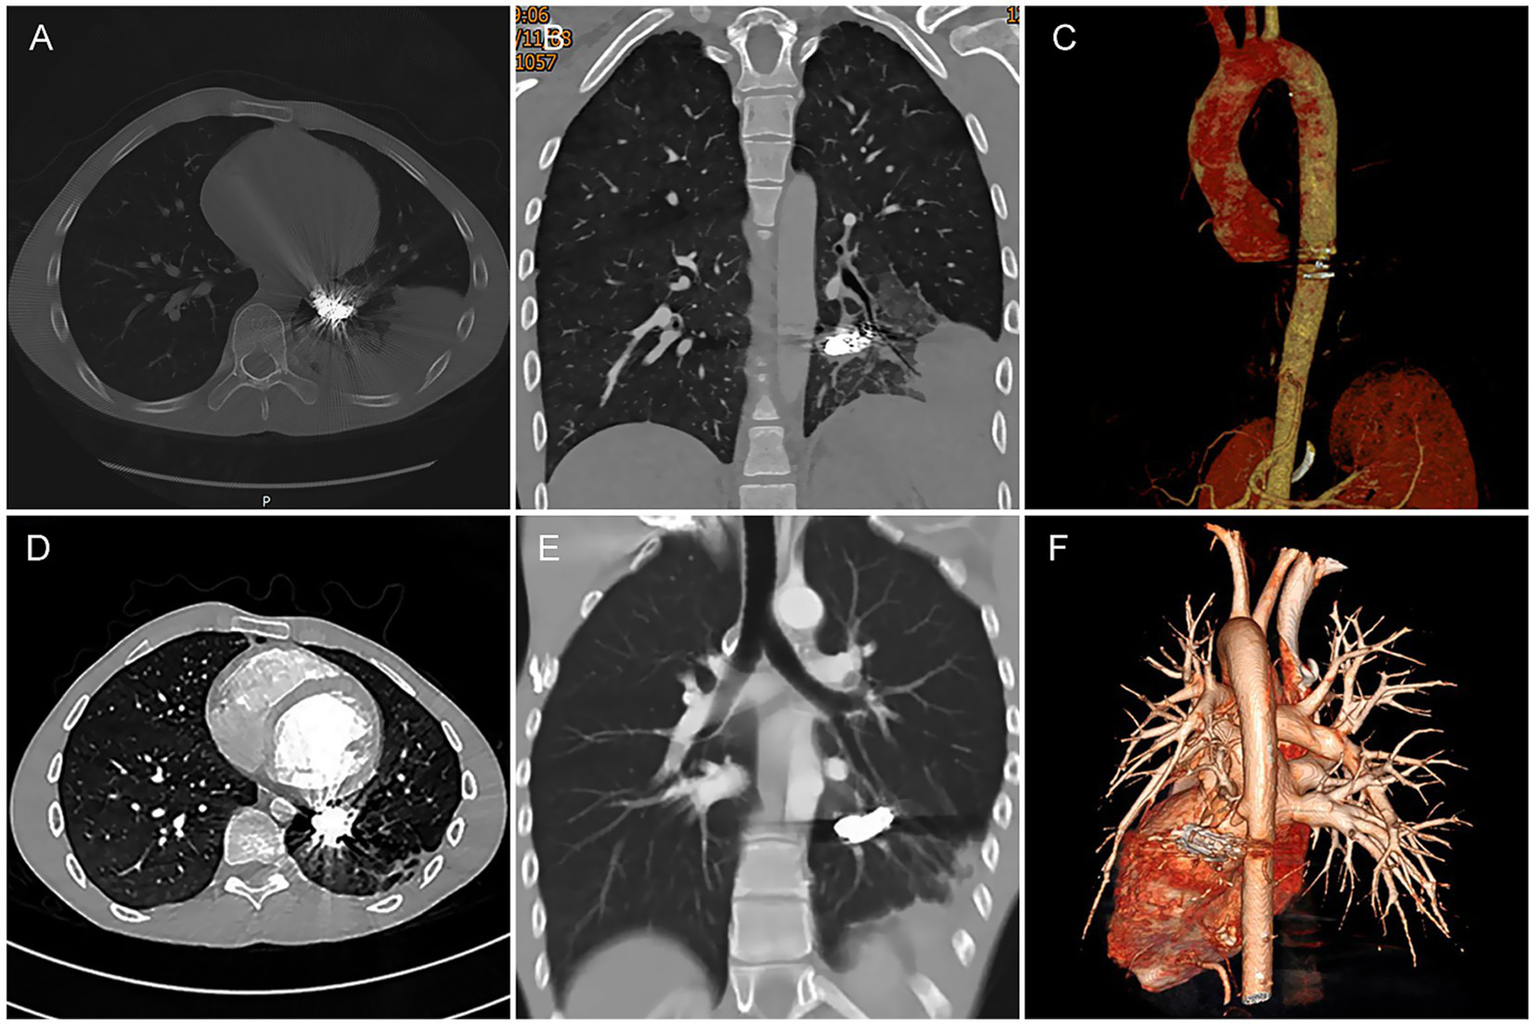

An 18-year-old male was admitted to the respiratory department due to “intermittent cough and hemoptysis for one day.” One day before admission, the patient developed a cough accompanied by hemoptysis (approximately 10 mL) after physical exertion, which resolved with rest. However, subsequently, even minor activity triggered coughing and hemoptysis, with a cumulative daily volume of nearly 100 mL, along with a sensation of a foreign body in the throat. He did not experience chills, high fever, dyspnea, or other discomforts. His past medical history was unremarkable except for rickets. Physical examination revealed coarse breath sounds and moist rales in the left lower lung. Laboratory tests showed no significant abnormalities. However, initial CT demonstrated hazy opacities in the left lower lobe, suggestive of pulmonary infection with alveolar hemorrhage. Additionally, abnormally dilated vessels and a localized soft tissue nodule (Figure 1A) raised suspicion of a vascular malformation. Consequently, a chest CTA was performed, revealing a large aberrant artery (maximum diameter: 1.2 cm) originating from the distal thoracic aorta and coursing through the left lower lobe, accompanied by patchy consolidation and ground-glass opacities (Figure 1B). The affected lung tissue maintained normal architecture and bronchial connectivity (Figures 1C,D). After multidisciplinary consultation involving radiology, interventional vascular surgery, and thoracic surgery, the patient was diagnosed with ASALLL. Following detailed informed consent, he opted for endovascular treatment.

Figure 1

CT imaging findings of the patient’s chest. (A) On CT lung window settings, patchy hazy opacities are visible in the left lower lobe, with abnormally dilated and tortuous vessels forming a localized soft tissue nodule (indicated by red arrow). (B) A markedly enlarged anomalous artery originating from the distal thoracic aorta is observed coursing through the left lower lobe parenchyma (red arrows), accompanied by patchy consolidation and ground-glass opacities in the left lower lobe. (C,D) CT coronal reconstruction and 3D bronchial tree rendering demonstrate normal continuity between the left lower lobe bronchus and the native bronchial tree (yellow arrows).